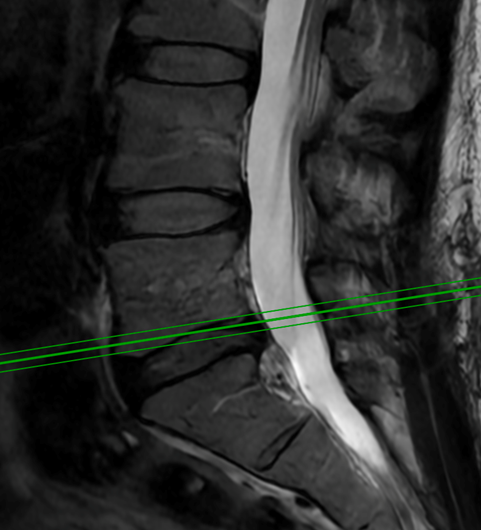

Spine:

Thoracic Spinal Cord Tumor Case Presentation

Author: Xavier P. J. Gaudin D.O., F.A.C.O.S., Read More!